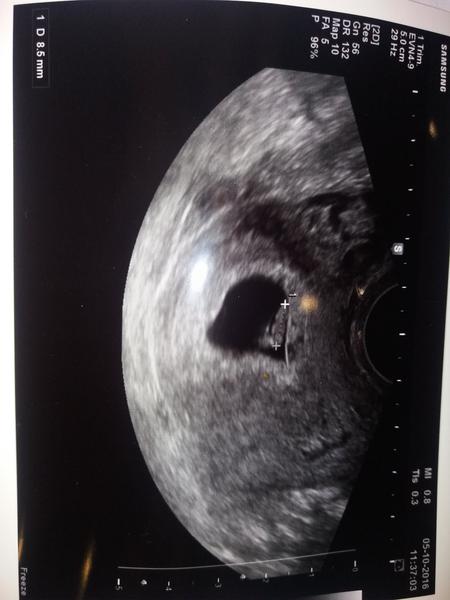

A tady nase zlaticko, ma 8,5mm,bohuzel se ji neukazalo na kolik odpovida,pristi ctvrtek kontrola,ten bude nejkrizovejsi rikala,zatim jsme ze 7 do 8tt neprelezli,tak se musim modlit.